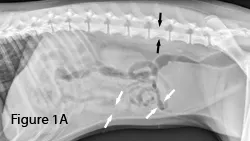

In dogs, a ratio of 1.6:1 for small intestinal diameter (white arrows) relative to height of fifth lumbar (L5) vertebral body (black arrows) is the upper limit of normal intestinal diameter for clinical use.2 A small intestine:L5 ratio that is >1.6:1 and/or a mixed bowel population (some normal, some distended segments) may indicate obstruction.

In cats, normal small intestinal diameter (between white arrows) is considered ≤1.2 cm from serosal to serosal surface.7